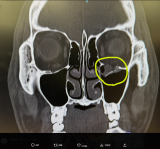

- YA-MANが公開したレントゲン。左目の下の骨がポッキリ折れている(@yaman_kosf)

- 左目が下がり、複視が起きるという@tonde_yamanより